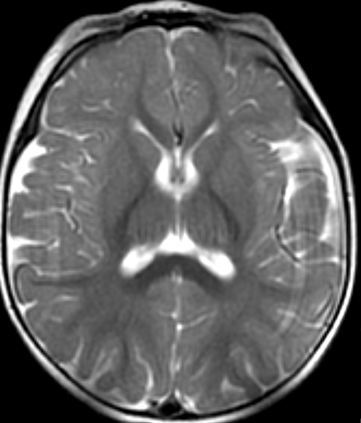

Blüml and colleagues have been studying preterm infants to learn more about how premature birth might cause changes in brain structure that may be associated with clinical problems observed later in life. Much of the focus has been on the brain's white matter, which transmits signals and enables communication between different parts of the brain. While some white matter damage is readily apparent on structural magnetic resonance imaging (MRI), Blüml's group has been using magnetic resonance spectroscopy (MRS) to look at differences on a microscopic level.

In this study, the researchers compared the concentrations of certain chemicals associated with mature white matter and gray matter in 51 full-term and 30 preterm infants. The study group had normal structural MRI findings, but MRS results showed significant differences in the biochemical maturation of white matter between the term and preterm infants, suggesting a disruption in the timing and synchronization of white and gray matter maturation. Gray matter is the part of the brain that processes and sends out signals.